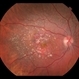

- CRAO, takayasu arteritis, calcified drusen

- Fundus fluorescein angiography image of a young girl with diagnosed Takayasu arteritis who presented with complains of diminished vision in both eyes. FFA shows complete absence of venous filling with segmented blood column secondary to CRAO with peripheral avascular area.